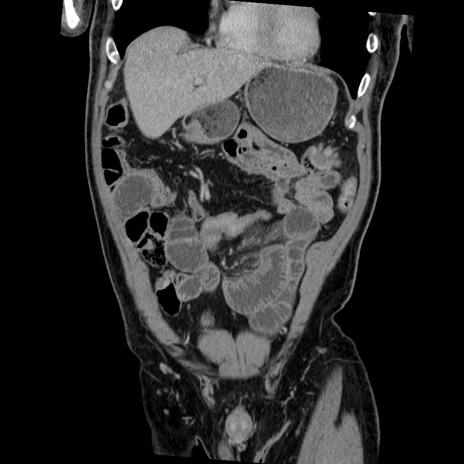

症例22(冠状断像)

【症例】50歳代男性

【主訴】腹痛

【現病歴】AVMからの被殻出血のため回復期リハ病棟入院中。 本日午後3時頃急に下腹部痛が出現した。

【既往歴】AVM、被殻出血、虫垂炎、高血圧

【身体所見】意識晴明、左半身不全麻痺、会話の理解は良好、36.5°C、腹部:膨隆、全体に板状硬、下腹部正中に圧痛点あり、反跳痛-、筋性防御不明、右下腹部にope scar

【データ】WBC 9400、CRP 0.06

横断像